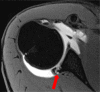

Figures